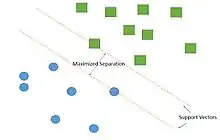

After pre-processing of funduscopic image, the image will be further analyzed using different computational methods. However, the current literature agreed that some methods are used more often than others during vessel segmentation analyses. These methods are SVM, multi-scale, vessel-tracking, region growing approach, and model-based approaches.

Support vector machine is by far the most frequently used classifier in vessel segmentation, up to 90% of cases.[82] SVM is a supervised learning model that belongs to the broader category of pattern recognition technique. The algorithm works by creating a largest gap between distinct samples in the data. The goal is to create the largest gap between these components that minimize the potential error in classification.[83] In order to successfully segregate blood vessel information from the rest of the eye image, SVM algorithm creates support vectors that separate the blood vessel pixel from the rest of the image through a supervised environment. Detecting blood vessel from new images can be done through similar manner using support vectors. Combination with other pre-processing technique, such as green channel filtering, greatly improves the accuracy of detection of blood vessel abnormalities.[76] Some beneficial properties of SVM include[83]